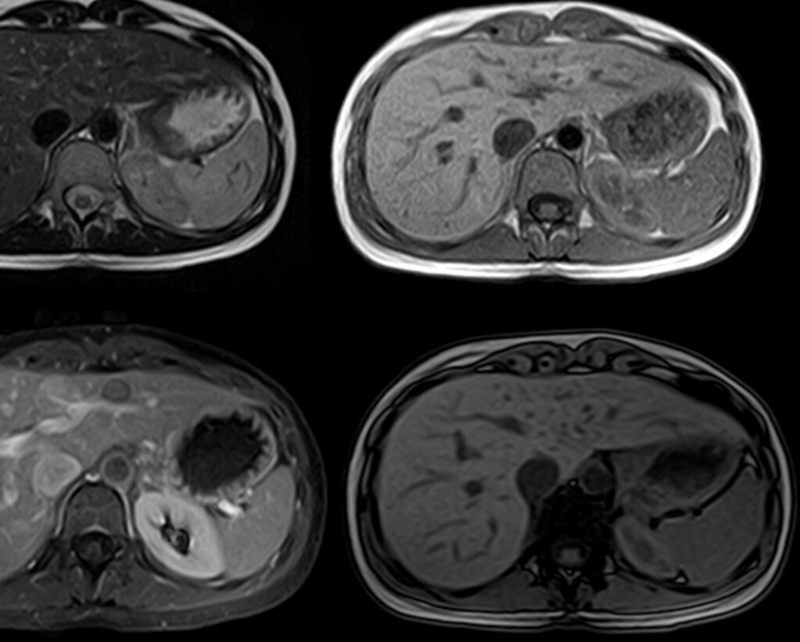

Mặc dù hai kỹ thuật chẩn đoán hình ảnh siêu âm và chụp CT được sử dụng phổ biến để chẩn đoán bệnh về gan nhưng so với chụp MRI gan thì chụp MRI có phần vượt trội hơn. Điều này được lý giải bởi độ phân giải hình ảnh cao cộng thêm khả năng tương phản mô mềm tốt của chụp MRI có thể cung cấp các thông tin về tổn thương gan khu trú, di căn, bệnh đường mật, bệnh mạch máu gan, bao gồm cả các tổn thương nhỏ. Vậy chụp MRI gan là gì?

Chụp MRI gan hay chụp cộng hưởng từ gan là phương pháp chẩn đoán hình ảnh mô phỏng lại hình ảnh của gan thông qua việc sử dụng từ trường mạnh, sóng vô tuyến và máy tính. Việc chụp MRI kết hợp với sử dụng thuốc tương phản còn cải thiện tốt hơn khả năng mô tả đặc điểm của tổn thương ở gan.